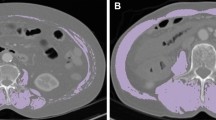

254 ASUC patients undergoing CT scans at admission were retrospectively included. Sarcopenia was assessed by the skeletal muscle index (SMI) with CT scans at L3, and patients with an SMI below the lowest sex-specific quartile were diagnosed with sarcopenia. Body mass index (BMI) < 18.5 kg/m2 was defined as clinical malnutrition. Univariate and multivariate analyses were performed to determine the association between sarcopenia and colectomy.

The prevalence of sarcopenia in ASUC was 50.0%, and malnutrition was 25.2%. Among sarcopenic patients, 36.2% was malnutrition, 51.2% had normal BMI, 11.8% was overweight, and 0.8% was obese. During index hospitalization, 66.9% patients needed rescue therapy with 52.4% received medical rescue therapy and 14.6% received colectomy. During follow-up, 33.2% patients needed colectomy. Significantly more sarcopenic patients required colectomy (22.0% vs 7.1%, p = 0.001) and rescue therapy (81.9% vs 52.0%, p < 0.001) during index hospitalization and colectomy during follow-up (44.4% vs 23.7%, p = 0.001) than non-sarcopenic patients. However, BMI < 18.5 kg/m2 was not related to the clinical course. In multivariate analyses, sarcopenia remained an independent risk factor for rescue therapy and colectomy during index hospitalization and colectomy during follow-up.